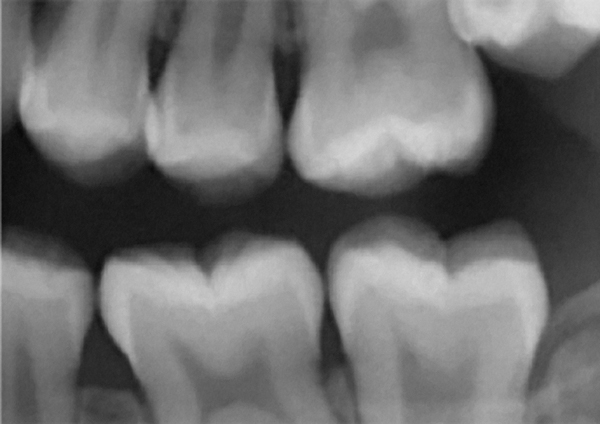

CBCT can also be used in this same manner to perform an even more common task, bitewing images, which are clinically indicated as often as every 18 to 24 months. For hygiene patients whose films require updating, CBCT offers a “patient-friendly” approach. Given that these films, which are usually performed intraorally, are often taken on an hourly basis in the typical general practice, the technology can be well utilized while also increasing comfort and satisfaction among patients. In addition, due to the expanded field of view that can be achieved with these extraoral CBCT images, they can often be more diagnostically valuable than images produced with an intraoral sensor (Figure 1 and Figure 2).

Figure 1 Traditional intraoral bitewing showing limited field of view (Fig 1) compared to the expanded view possible using CBCT (Fig 2).

Figure 2 Traditional intraoral bitewing showing limited field of view (Fig 1) compared to the expanded view possible using CBCT (Fig 2).